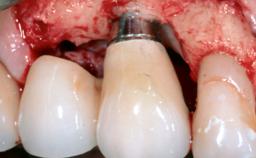

Paolo Casentini demonstrates that peri-implantitis can be successfully treated even at an advanced stage. He discusses a case in which the existing implants and prostheses were both retained while regenerating the defect and creating a band of keratinized tissue. A 69-year-old female patient was referred by her general dentist for evaluation of a recurrent infection at previously placed and restored implants in the posterior left mandible. The patient’s chief complaint was recurrent swelling and pain in the molar region of the left posterior mandible with discomfort during brushing in the same area. The patient reported receiving two implants (36 and 37) nine years earlier.